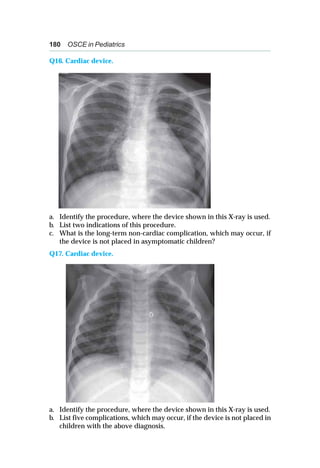

likely diagnosis?

Q26. A 35-week-old female is born via elective LSCS. She cried soon

after birth and did not require any resuscitation. She is born to a

primigravida mother, who had no risk factors for sepsis. She developed

tachypnea soon after birth with mild to moderate subcostal recessions.

a. List two positive findings on chest X-ray.

b. What is the likely diagnosis?

c. What is prognosis?